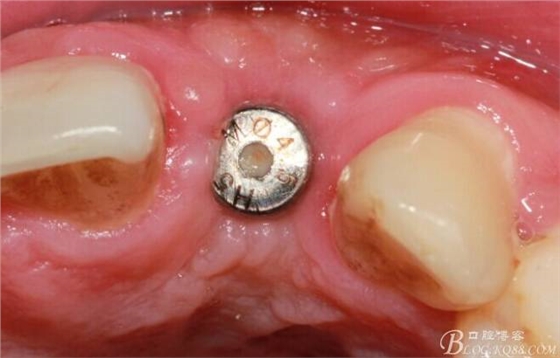

事實證明,我的做法沒有錯誤,一個月后,軟組織健康愈合。鄰牙軟組織沒有退縮。

再次翻瓣。